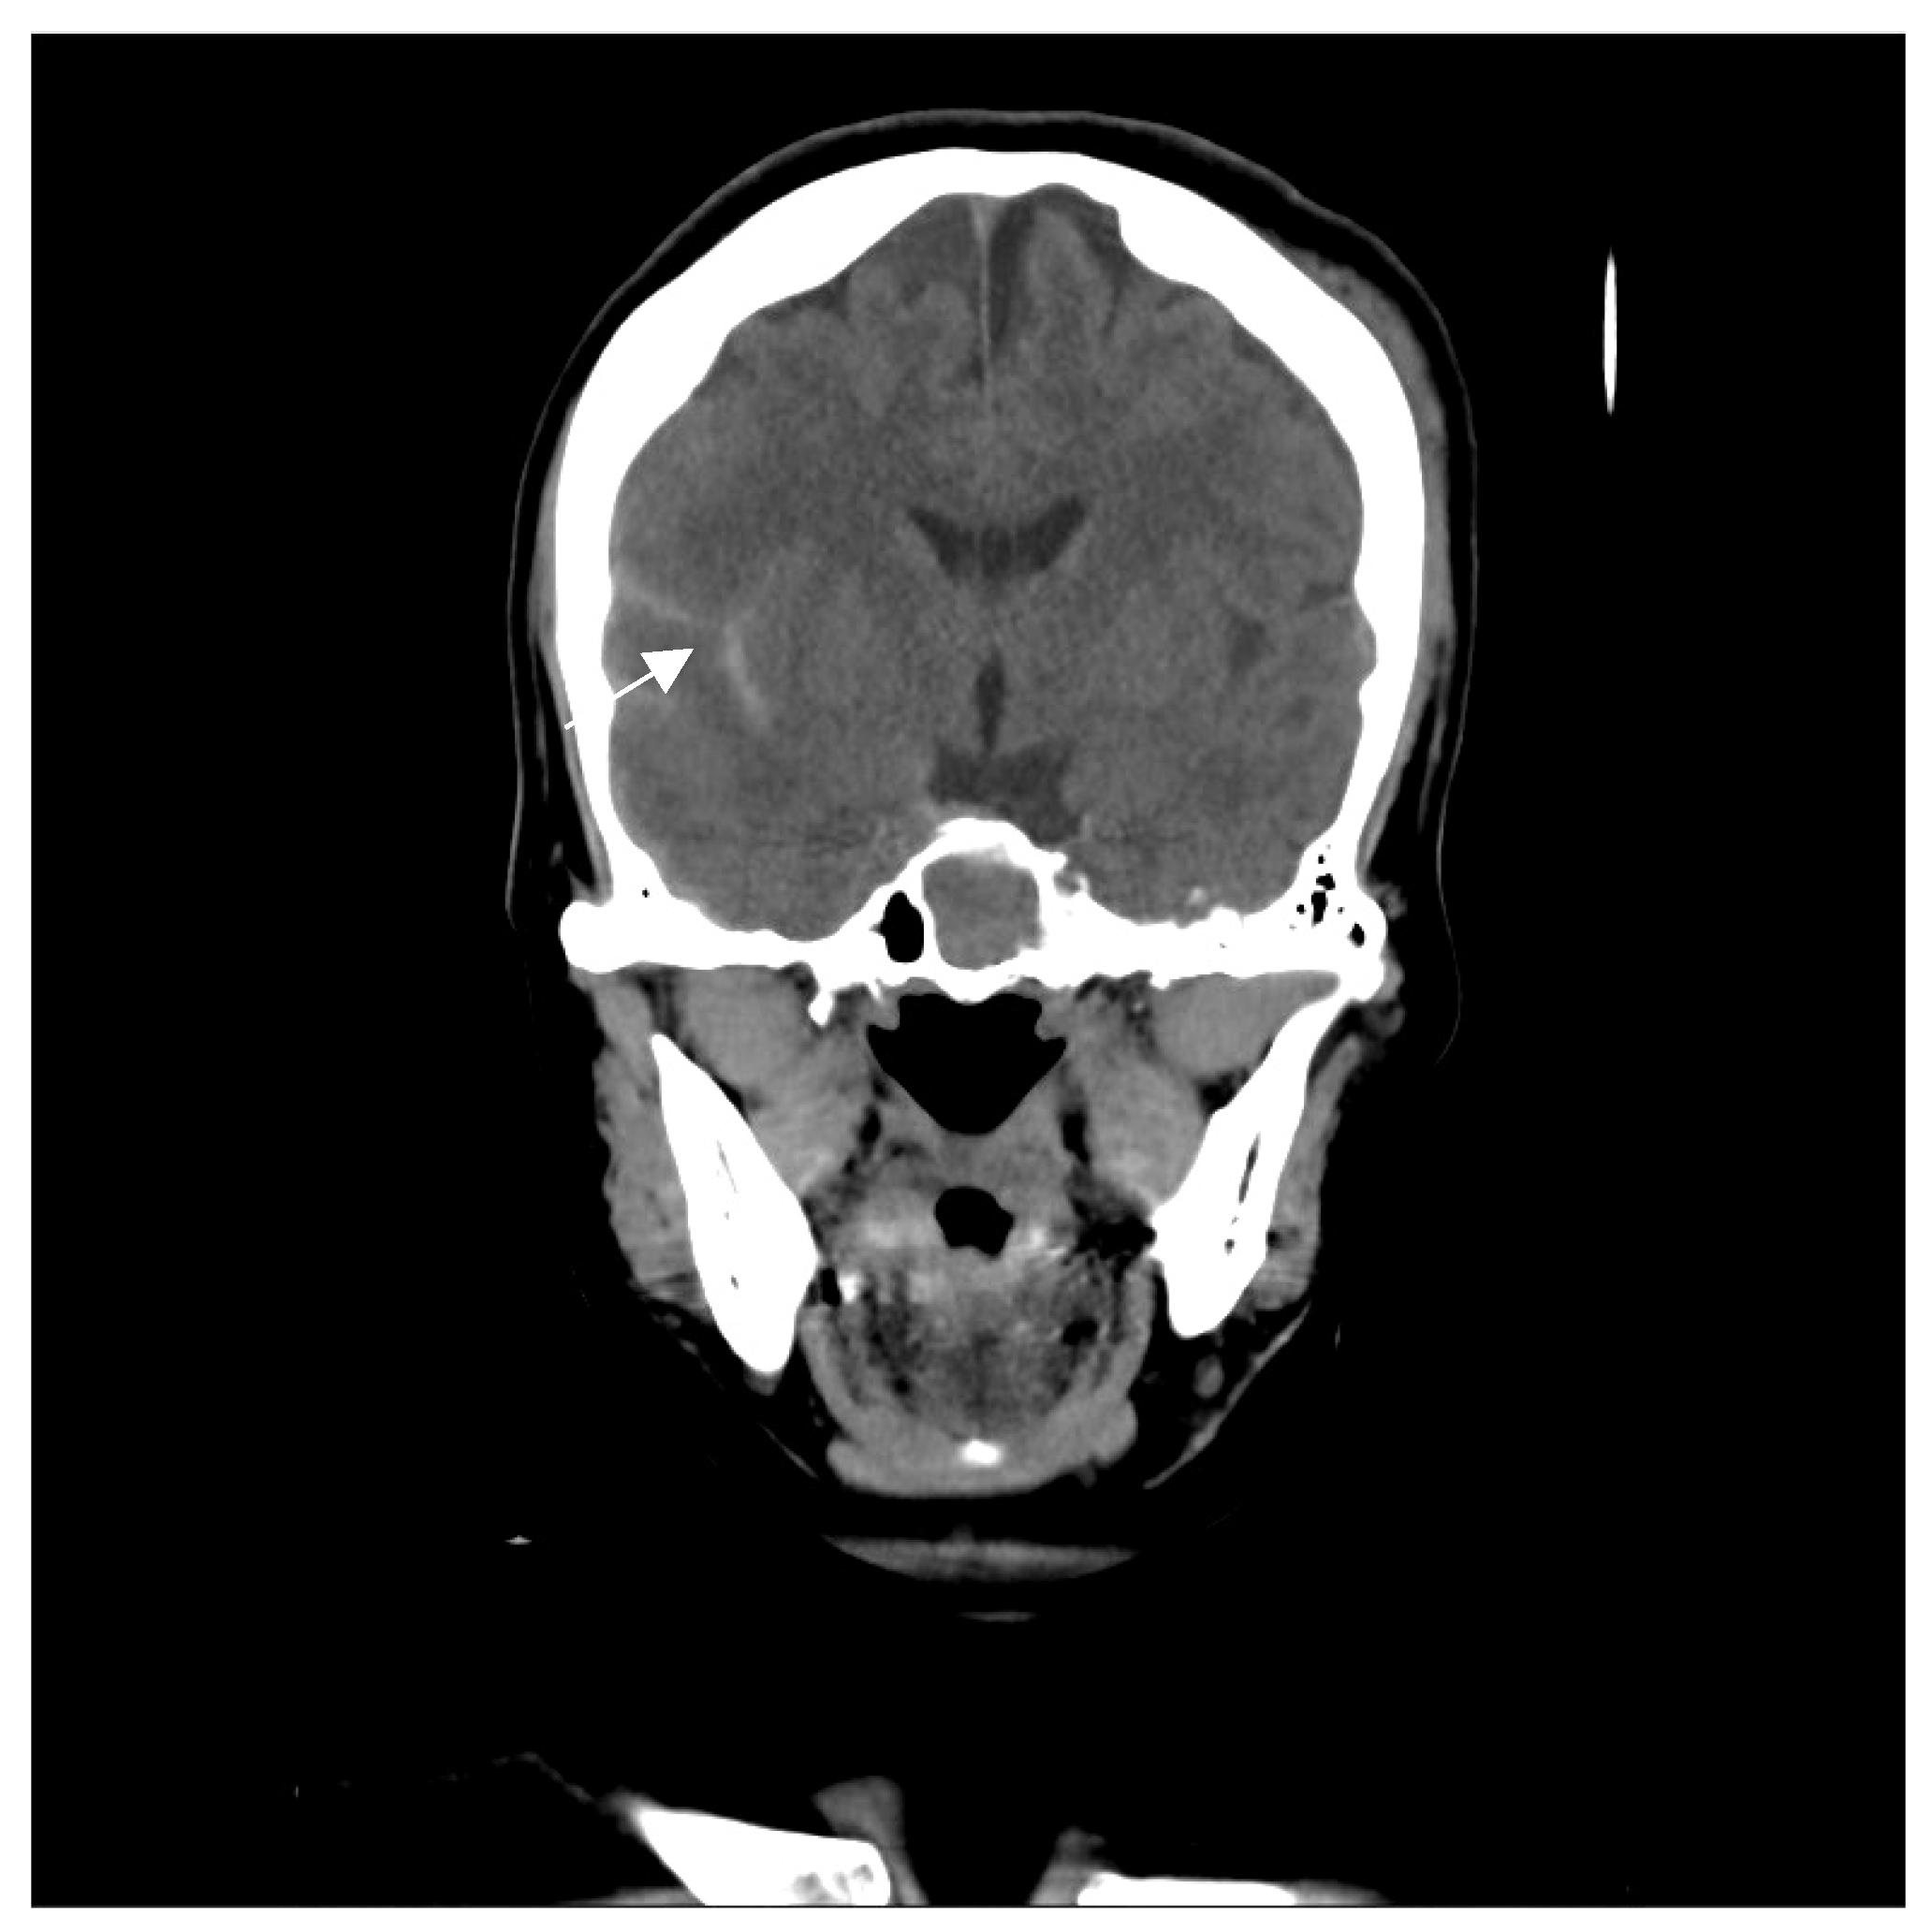

2. Case Report